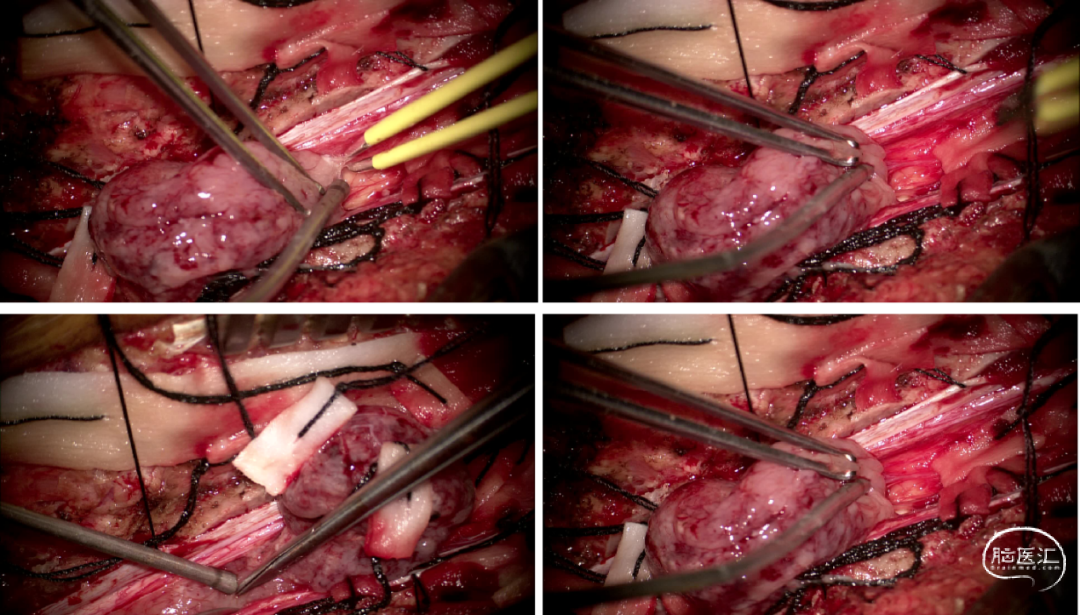

手术情况

硬脊膜张力高,脊髓向背侧膨出,与脊髓腹侧粘连紧密,肿瘤挤压脊髓,肿瘤边界分离,减少对胸髓的牵拉,降低了术后患者神经功能发生的概率,术后患者肢体麻木症状改善。